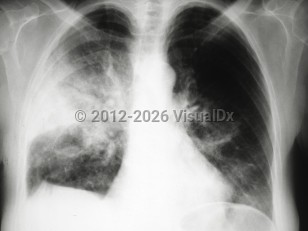

Fever, Cough, 50-59 year old Female

COVID-19